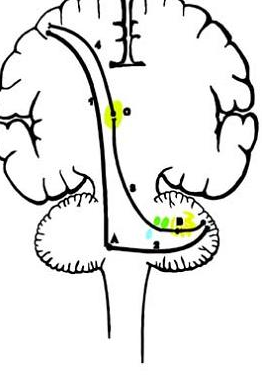

In the brainstem lateral corticospinal axons descend on the same side as their cortical origin until the

pyradmial decussation in the caudal medulla

which corticospinal tract continues ipsilaterally?

anterior corticospinal tract (only 15%)